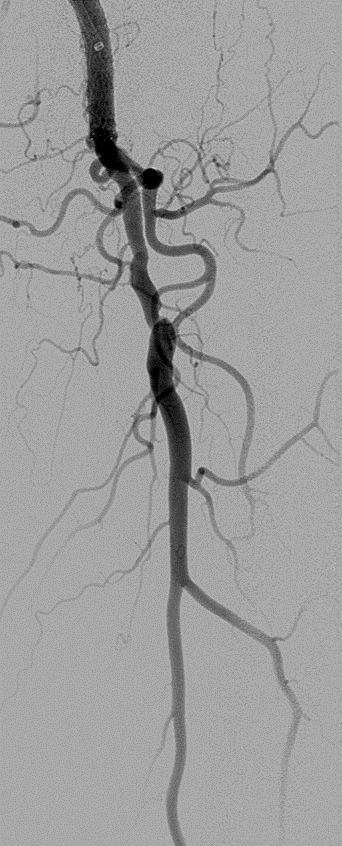

★ Case 6

Severecalcification

左右滑动查看